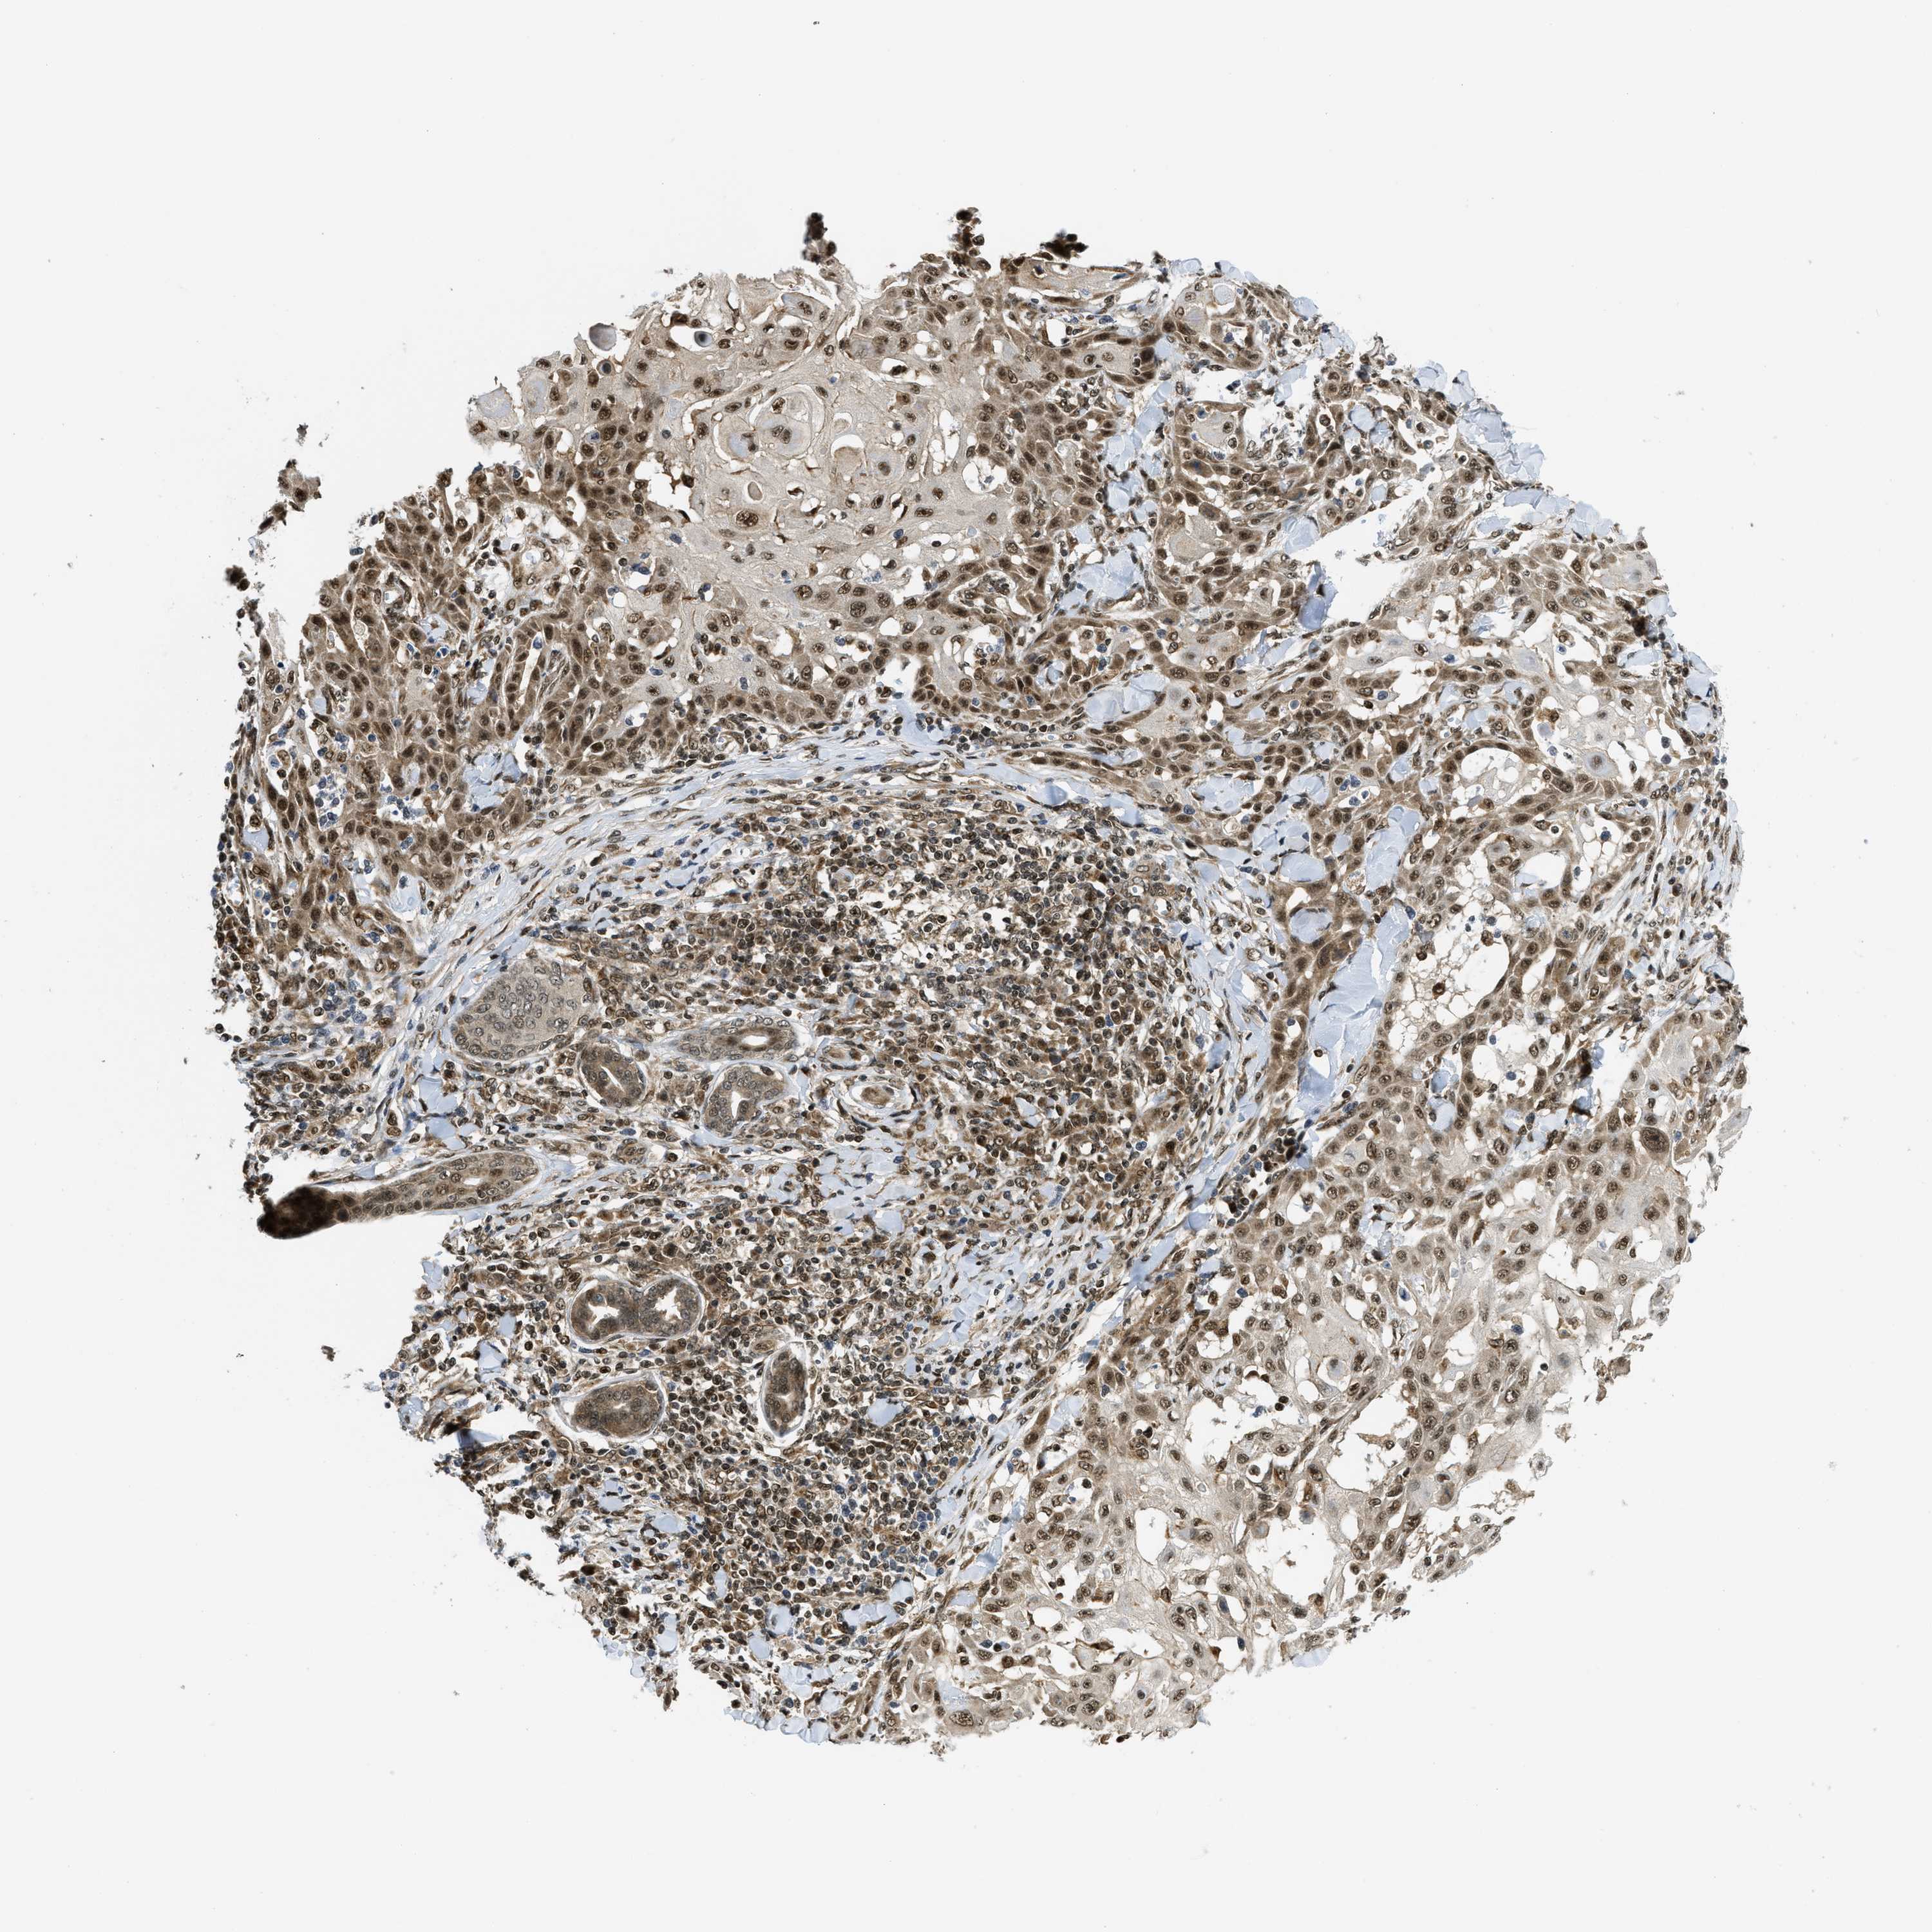

SKIN CANCER - Protein expressioni

A mouse-over function shows sample information and annotation data. Click on an image to view it in a full screen mode. Samples can be filtered based on level of antibody staining by selecting one or several of the following categories: high, medium, low and not detected. The assay and annotation is described here.

Each image is clickable and will lead to virtual microscopy that enables deeper exploration of all samples and also displays staining intensity scores, fraction scores and subcellular localization as well as patient and tissue information for each sample.

Antibody HPA024702

Antibody CAB017041

Staining

High

Medium

Low

Not detected

Intensity

Strong

Moderate

Weak

Negative

Quantity

>75%

75%-25%

<25%

None

Location

Nuclear

Cytoplasmic/membranous

Cytoplasmic/membranous,nuclear

Basal cell carcinoma

Squamous cell carcinoma, NOS

Squamous cell carcinoma, metastatic, NOS